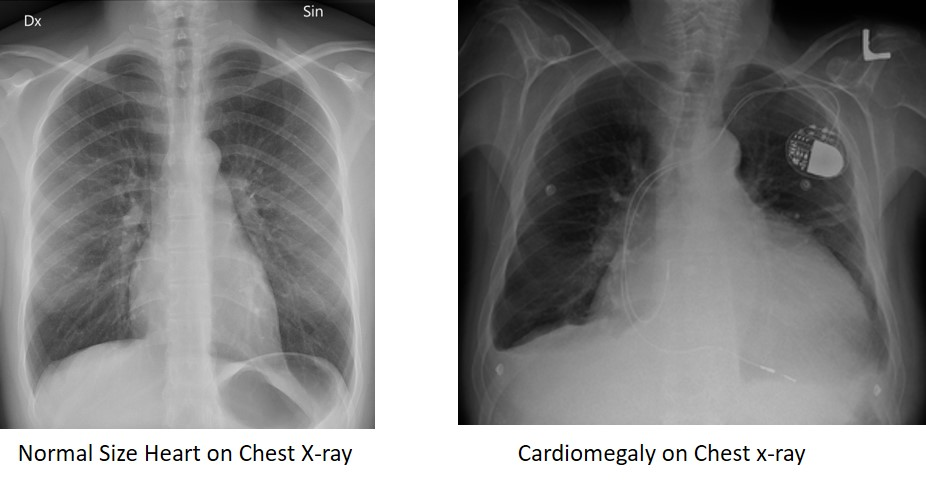

2. Chest Xray

<ol><li><p><span style="color: rgb(153, 107, 14);"><strong>BNP!!</strong></span></p></li></ol><ul><li><p><span style="color: rgb(153, 107, 14);">&lt; 100 safe</span></p></li><li><p><span style="color: rgb(153, 107, 14);">elevated = HF</span></p></li></ul><p></p><ol start="2"><li><p><span style="color: rgb(203, 68, 215);"><strong>Echocardiogram</strong></span></p><ul><li><p>shows EF&nbsp;</p><p></p></li></ul></li><li><p><span style="color: rgb(7, 153, 50);"><strong>Chest Xray</strong></span></p></li></ol><p></p>

What does chest xray show in HF? (2)

1. Cardiomegaly

• enlarged heart

1. Pulmonary congestion

<ol><li><p><span style="color: rgb(195, 61, 232);"><strong>Cardiomegaly</strong></span></p></li></ol><ul><li><p><span style="color: rgb(195, 61, 232);">enlarged heart</span></p></li></ul><ol start="2"><li><p><span style="color: rgb(134, 145, 232);"><strong>Pulmonary </strong></span>congestion</p></li></ol><p></p>

1. CXR: pulmonary congestion